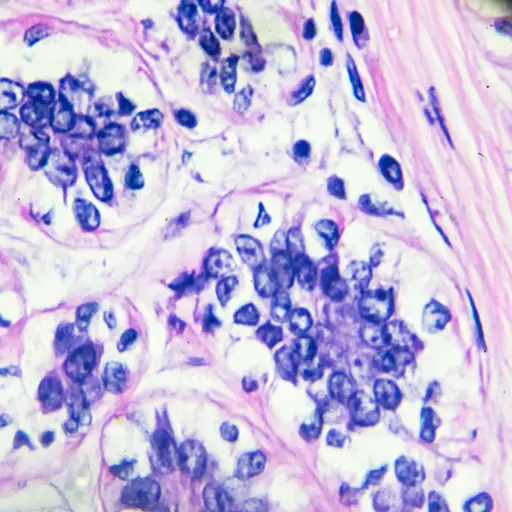

理解转移性乳腺癌癌症并不容易。首先,这不是一种特定的乳腺癌,而是最晚期的乳腺癌(称为第四期):癌细胞已经从乳房扩散到身体的其他部位。有些人第一次被诊断为转移性乳腺癌,但这并不典型。最常见的是,转移性乳腺癌是在你完成早期乳腺癌的治疗后出现的。4期乳腺癌是你的错吗?这难道不意味着没有可以尝试的治疗方法了吗?没有,没有。为了更清楚地了解这种情况,让我们考虑一下这些和其他一些误区。

它能够令人困惑,但无论在身体上行驶,乳腺癌都会留下乳腺癌。“一些癌症在遗传上赋予了蔓延的能力,”斯基斯博士说。“这不是一场偶然的活动。乳腺癌细胞转到骨骼,因为它们被编程[待办事项]。如果他们从乳腺到骨骼,癌细胞仍然是乳腺癌,但患有骨癌的乳腺癌。“换句话说,在身体的不同部分中的转移性乳腺癌肿瘤仍然由乳腺癌细胞组成。